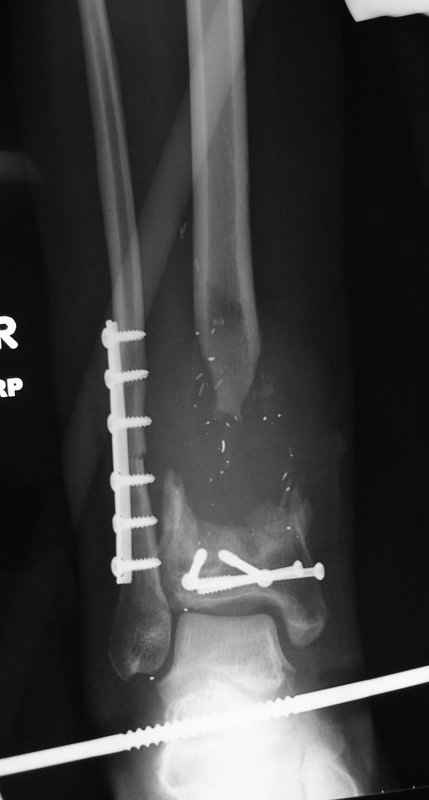

1 - рентгенограмма (прошу прощения за качество) при поступлении;

2 - внешний вид голени;

Произведено ПХО, acute shortening (5 см), фиксация стержневым аппаратом Hoffman.

3,4 - через 4 недели наложен спице-стержневой аппарат, произведена остеотомия большеберцовой кости в верхней трети, раны зажили, проводилась дистракция в аппарате.

5, 6 - через 2,5 мес после травмы выполнен закрытый остеосинтез блокируемым штифтом.

7, 8, 9, 10, 11 - через 8 мес после травмы перелом сросся.

Пациент ходит без дополнительной опоры, не хромает (видеоролик выложил сюда

http://rapidshare.com/files/14134274/Patient_B.AVI.html, вес 892 кб).